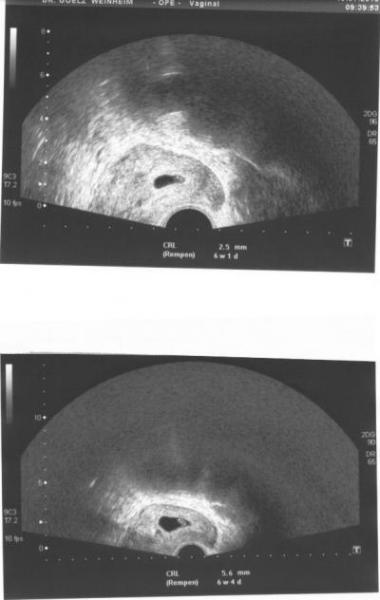

Halli, Hallo, Hallöchen. ... hatte heute nochmals Termin. Hatte schon schiss! Aber es ist alle o.k. Krümelchen wächst und hinterher war mir sogar schlecht! Hab jetzt in Drei Wochen wieder Termin zum ersten Screening! Bin heute 6+5 SSW , lt. US 6+4 ... aber genauer wirds dann das nächste mal. Hab noch meine zwei Bildchen vom 15.07 (5+5) (das obere)und von Heute. So ich werd mich jetzt mal verabchieden für die nächsten 12 tage, es geht nämlich nach "Malle". Ich werd mich schön erholen und alles nen guten Mann sein lassen. LG, Manu.

Bild zu ... zurück vom FA... und dann mal weg! - Forum für März - Mamis